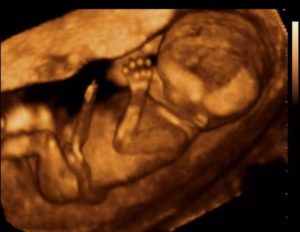

Многие будущие мамы предпочитают пройти 3д-сканирование – его принцип основан на таком же способе, как и обычное УЗИ, однако трехмерное изображение позволяет выявить пороки сердца и аномалии развития центральной нервной системы. Качественный снимок УЗИ в 14 недель позволяет разглядеть пропорциональное тело крохи, намечающийся волосяной покров на головке, брови и реснички, заметить выражение личика крохи и сходство с родителями.

Но отличаться 3д картинка от 2д будет существенно. На рисунке показаны примеры в двух режимах ультразвукового сканирования.

Рисунок 1. 2д

визуализация развивающегося ребёнка

Рисунок 2. 3д

хорошо определяются структуры лица

Как видно на приведенных выше примерах, изображение при двухмерном сканировании плоское, а разобрать детали на нем может только опытный профессионал. При трехмерном картинка больше напоминает своеобразное «фото» малыша.